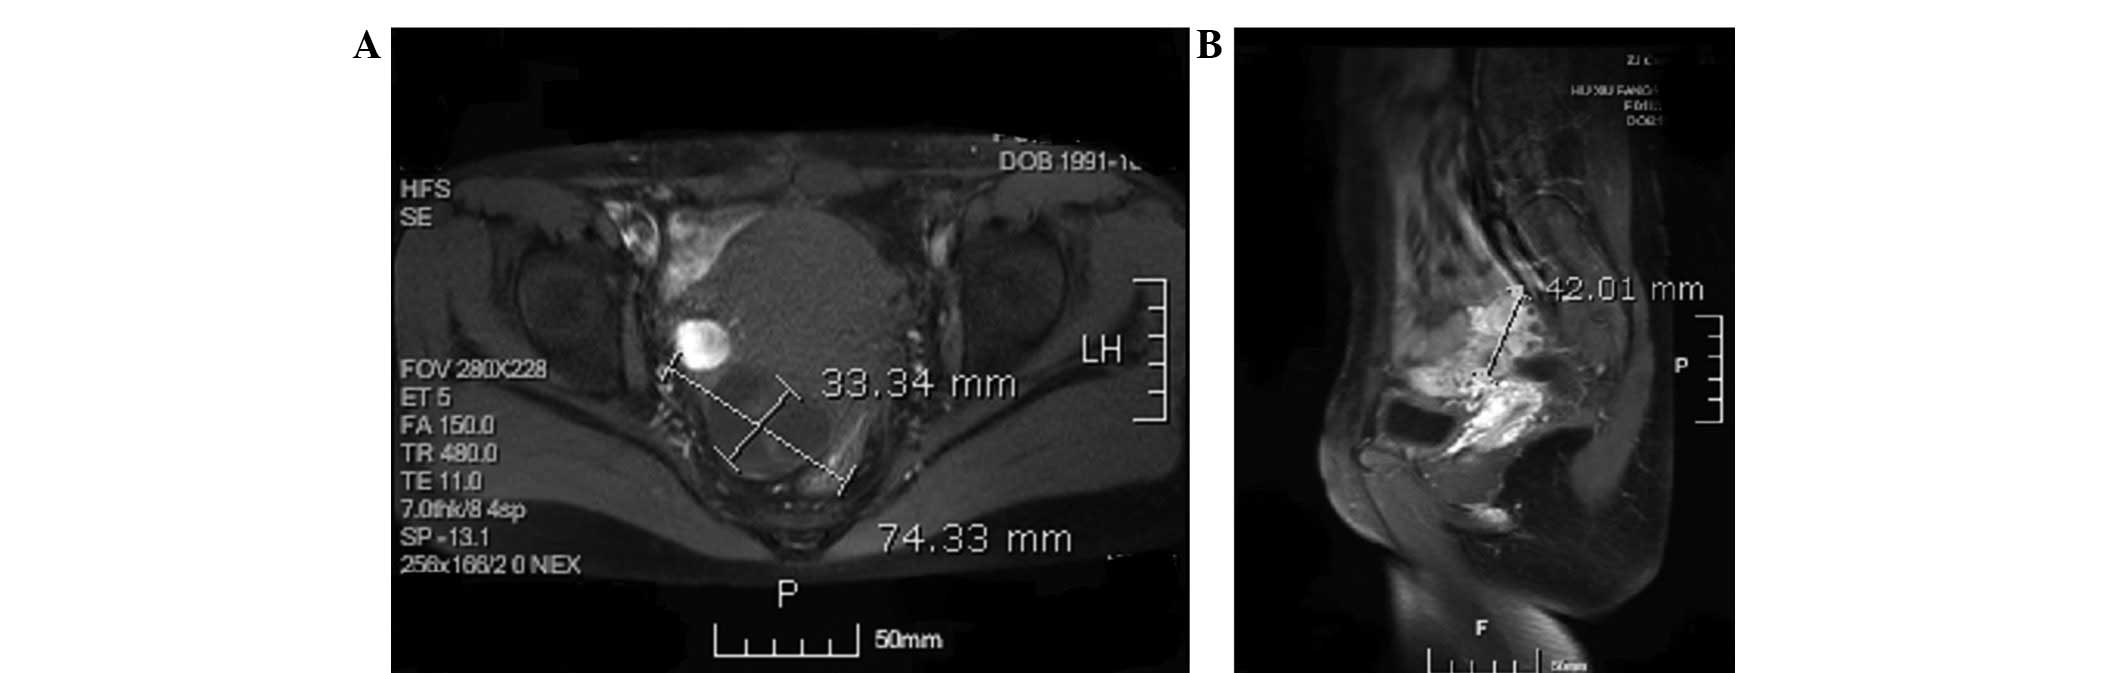

However, tumor recurrence occurred three months after the final BEP regimen. The serum AFP levels elevated to 193.99 ng/ml on June 4, 2010 and magnetic resonance imaging (MRI) revealed a cystic and solid mass in the right parametrium (Fig. 4). A salpingostomy and secondary cytoreductive surgery were performed on June 11, 2010. No residual tumor was found and the histology report showed metastatic or invasive malignant tumors (although a YST was initially considered) on the surface of the sigmoid colon and the rectum (Fig. 5). The patient underwent three cycles of chemotherapy consisting of bleomycin (15 mg for three consecutive days), vincristine (1.5 mg on day one) and cisplatin (40 mg for three consecutive days; termed a BVP regimen) and three cycles of chemotherapy consisting of vincristine (1.5 mg one day one) and cisplatin (40 mg for three consecutive days; termed a VP regimen). Following the final VP regimen on October 11, 2010, the AFP level decreased to 2.59 ng/ml and the CA-125, β-hCG, CEA, CA 19-9 and SCC were within the normal ranges.

Figure 4

Magnetic resonance imaging revealed a cystic and solid mass in the right parametrium, measuring 3.3×7.4×4.2 cm. The tumor diameter was (A) 3.3cm×7.4 cm in the transverse plane and (B) 4.2cm in the coronal plane.